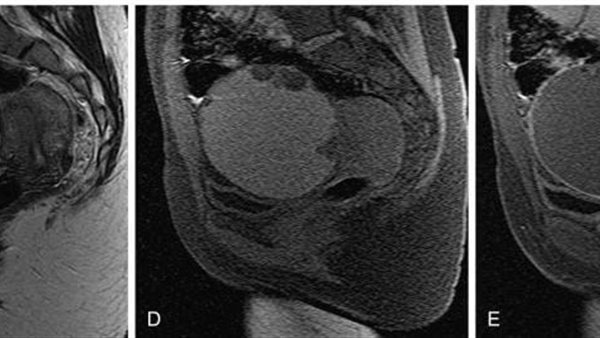

وقال الدكتور تامر مدكور، وكيل وزارة الصحة بالدقهلية، إن المريضة حضرت إلى عيادة جراحة الأورام وهي تعاني من آلام مستمرة بمنطقة الحوض، مع وجود تاريخ مرضي تضمن استئصالًا جزئيًا للرحم، وجراحة سابقة لاستئصال كيس على المبيض. وبناءً على الفحوصات والأشعة، تبيّن وجود كيس بحجم 10 سم في منتصف الحوض.

وأوضح “مدكور” أنه فور التشخيص، تم تجهيز المريضة لإجراء عملية استكشاف جراحي، تم خلالها فك الالتصاقات الناتجة عن العمليات السابقة، واستئصال الكيس الحوضي، إلى جانب كيس آخر على المبيض، بالإضافة إلى إصلاح فتق جراحي، مشيرًا إلى أن الفريق الطبي تعامل مع الحالة بكفاءة عالية حتى استقرت حالتها تمامًا.